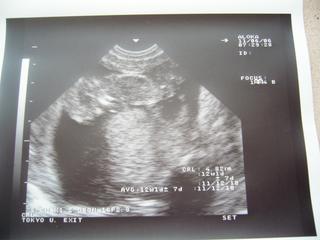

Inak, bola som v pondelok na poradni a USG, len som sa sem nejako nedostala. Pridávam fotky z USG. Zatiaľ mám - 2 kg. V pondelok som bola podľa menzesu 11+6 tt. Podľa USG má jedno 48,2 mm - to vychádza na 12+1 tt v pondelok a druhé 48,5 mm - a to bolo veľké na 12+2 tt., takže pekne rastieme. Na jednej je jedno, na druhej sú obe a na tretej je druhé. Jedno je dole hlavičkou a druhé bolo priečne.